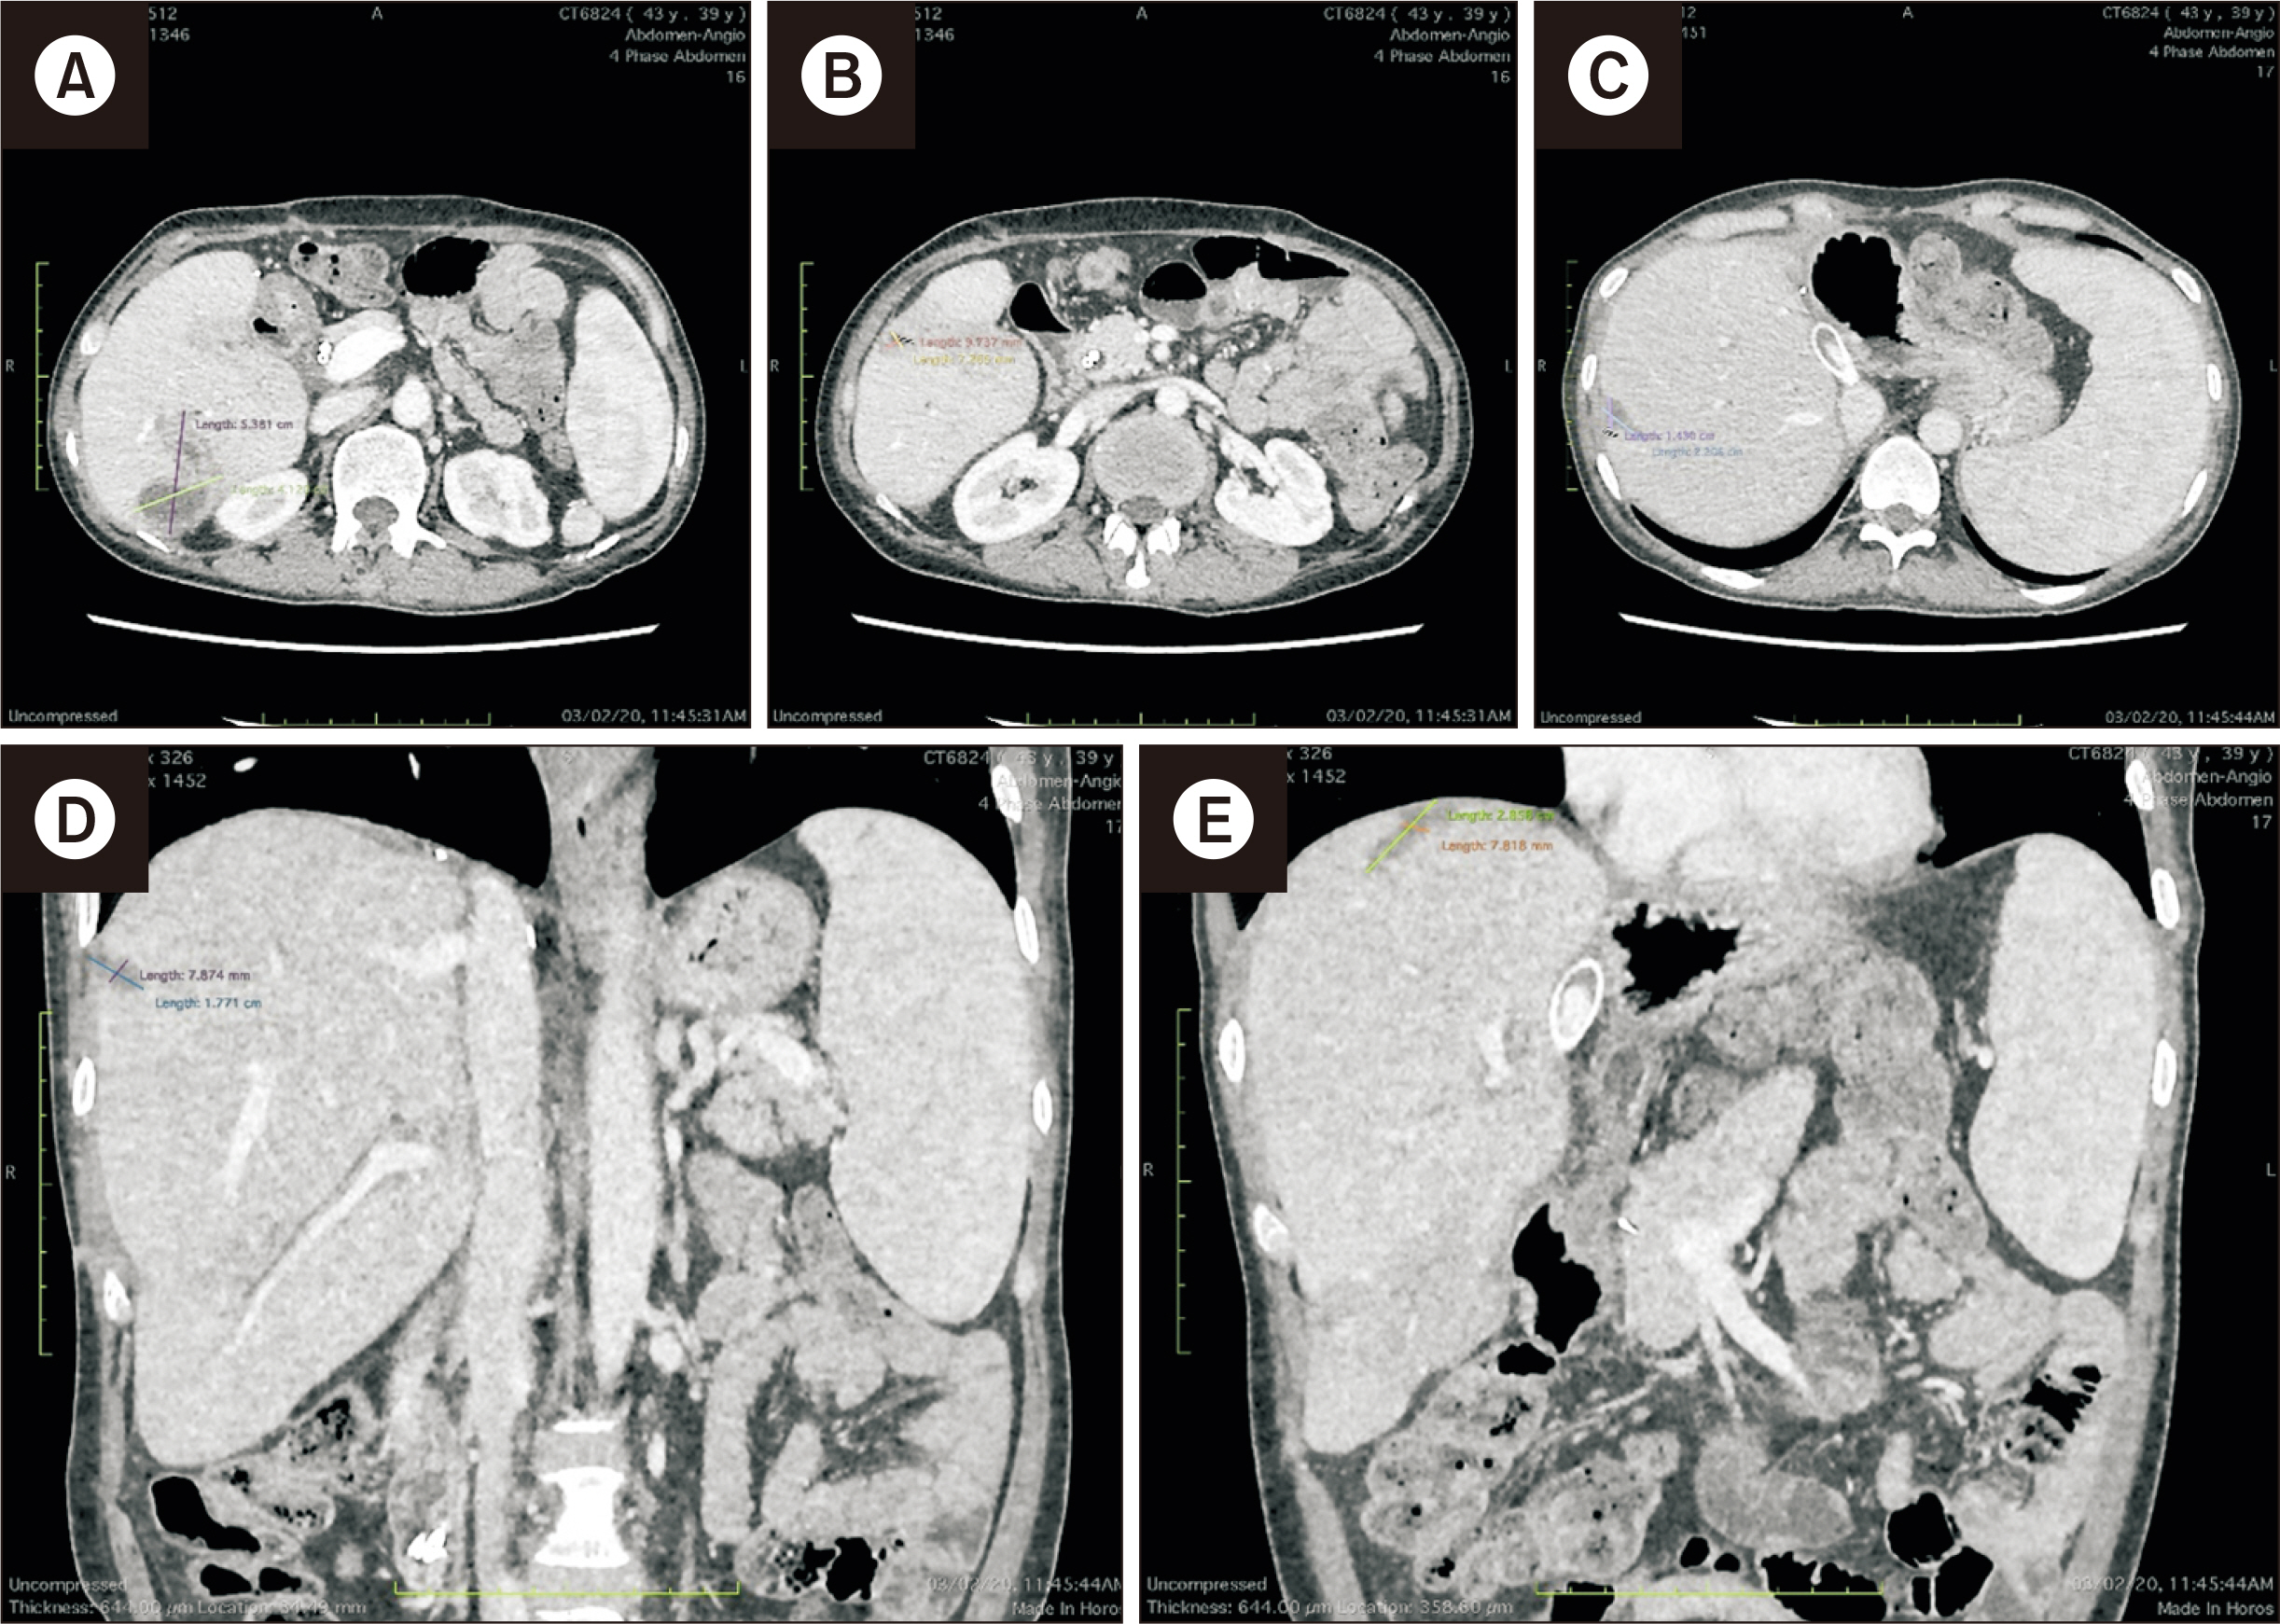

- Kaposi sarcoma following solid organ transplantation is a rare and underreported complication, with few cases documented globally concerning its origin from liver grafts. This case report describes an Asian woman who developed Kaposi sarcoma in a liver graft following living donor liver transplantation for end-stage liver disease resulting from hepatitis D virus. In accordance with current guidelines, standard immunosuppression was discontinued, and mammalian target of rapamycin (mTOR) inhibitors were initiated. The use of mTOR inhibitors led to the complete resolution of the liver graft lesions within 9 months. However, subsequent follow-up revealed several complications, including late anastomotic biliary stricture, extensively drug-resistant Klebsiella pneumoniae infection, and subtotal hydrothorax. These complications required intensive care unit admission, biliary stenting, oxygen therapy, and pleural drainage. Despite the severity of her condition, the patient fully recovered and showed no signs of recurrence throughout the 64-month follow-up period. To our knowledge, this is the first reported case of Kaposi sarcoma in a liver graft with such an extended follow-up.

Figure

Article10. Gupta S, Ghuman SS, Buxi TB, Sudarsan H, Sethi S, Yadav AK, et al. 2015; Imaging of Kaposi sarcoma in a transplanted liver: a rare case report. Egypt J Radiol Nucl Med. 46:335–8. DOI: 10.1016/j.ejrnm.2015.02.007.